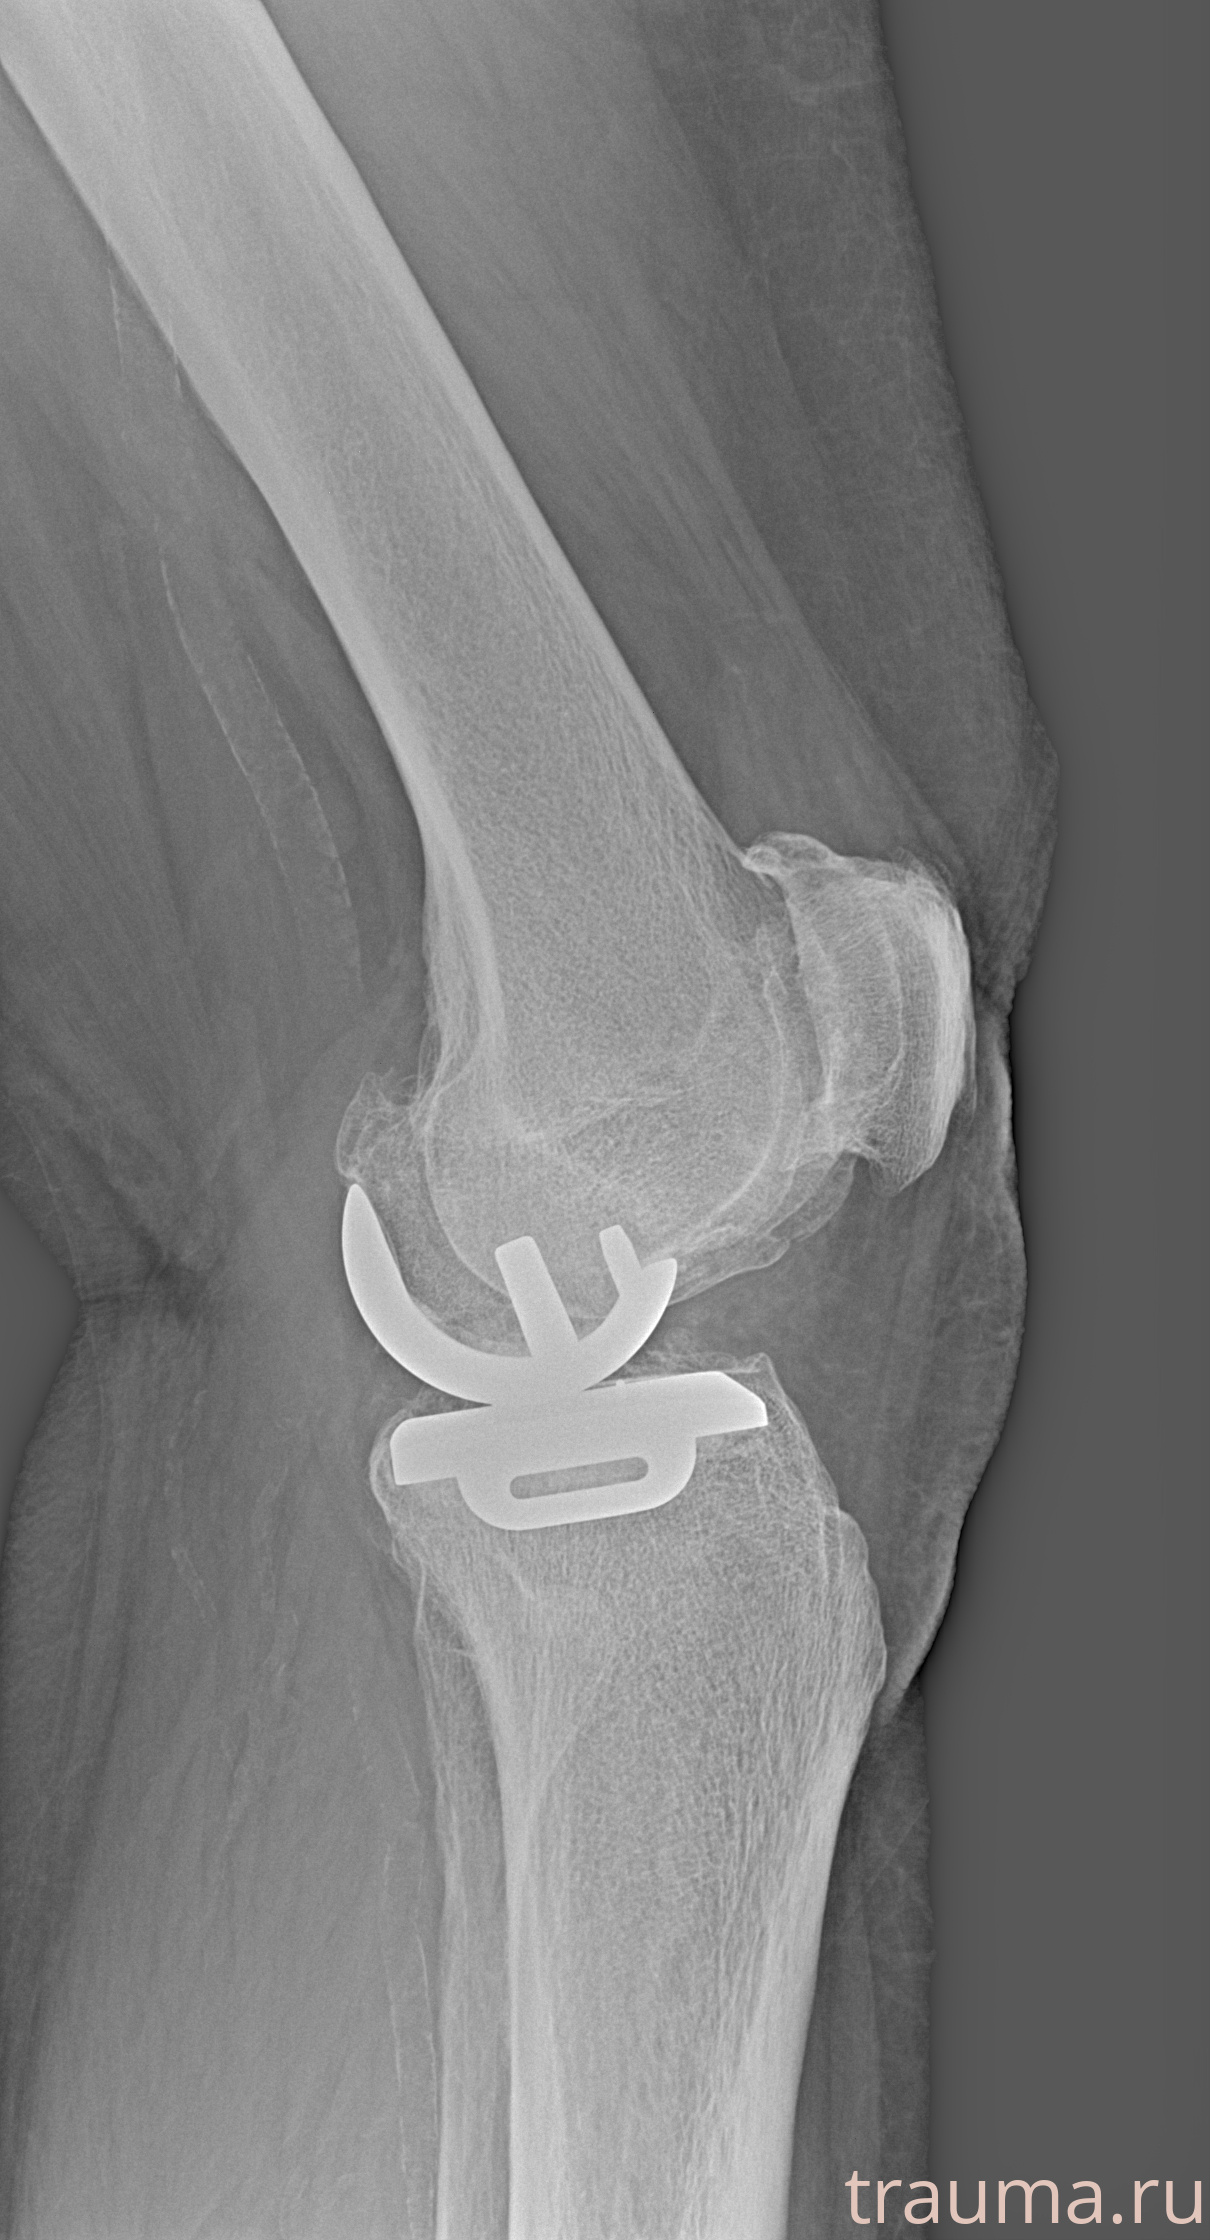

Правый

Рентгенограммы